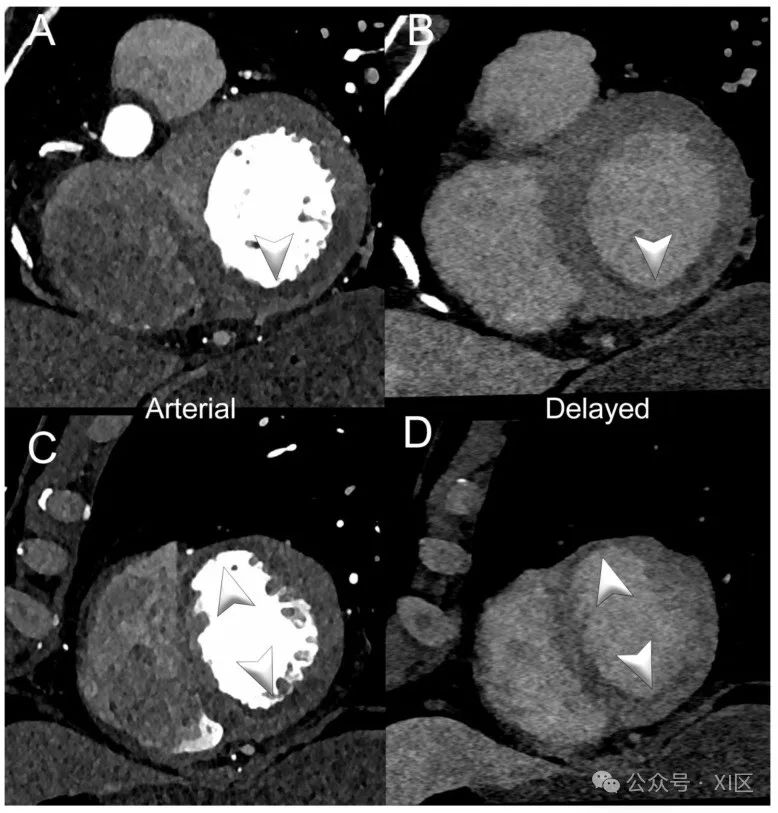

图3和图4展示了左心室缺血的PCCT示例。

图3 心脏/冠状动脉能谱PCCT示例,显示亚急性左心室缺血。图中展示了一位患有近期急性心肌梗死的患者,其右冠状动脉和左前降支冠状动脉领域的能谱CTA。A,B显示左心室(LV)基底短轴视图,分别为动脉/血管造影相位(A)和延迟相位(B);C,D显示LV心尖部位的相同信息。箭头指示多个LV段的低灌注(早期和延迟)。延迟相位采用了能谱采集和40 KeV重建。扫描使用商用全身双源PCCT扫描仪(NAEOTOM Alpha,Siemens Healthineers)进行,层厚为0.2/0.4mm,重建间隔为0.1/0.2mm,FOV 140–160mm,源轴向重建的分辨率矩阵为512 × 512/1024 × 1024,使用Bv48-60卷积核和最大强度的量子迭代重建(QIR 4);扫描采用回顾性心电门控和管电流调制。显示的空间分辨率为0.1/0.20mm。